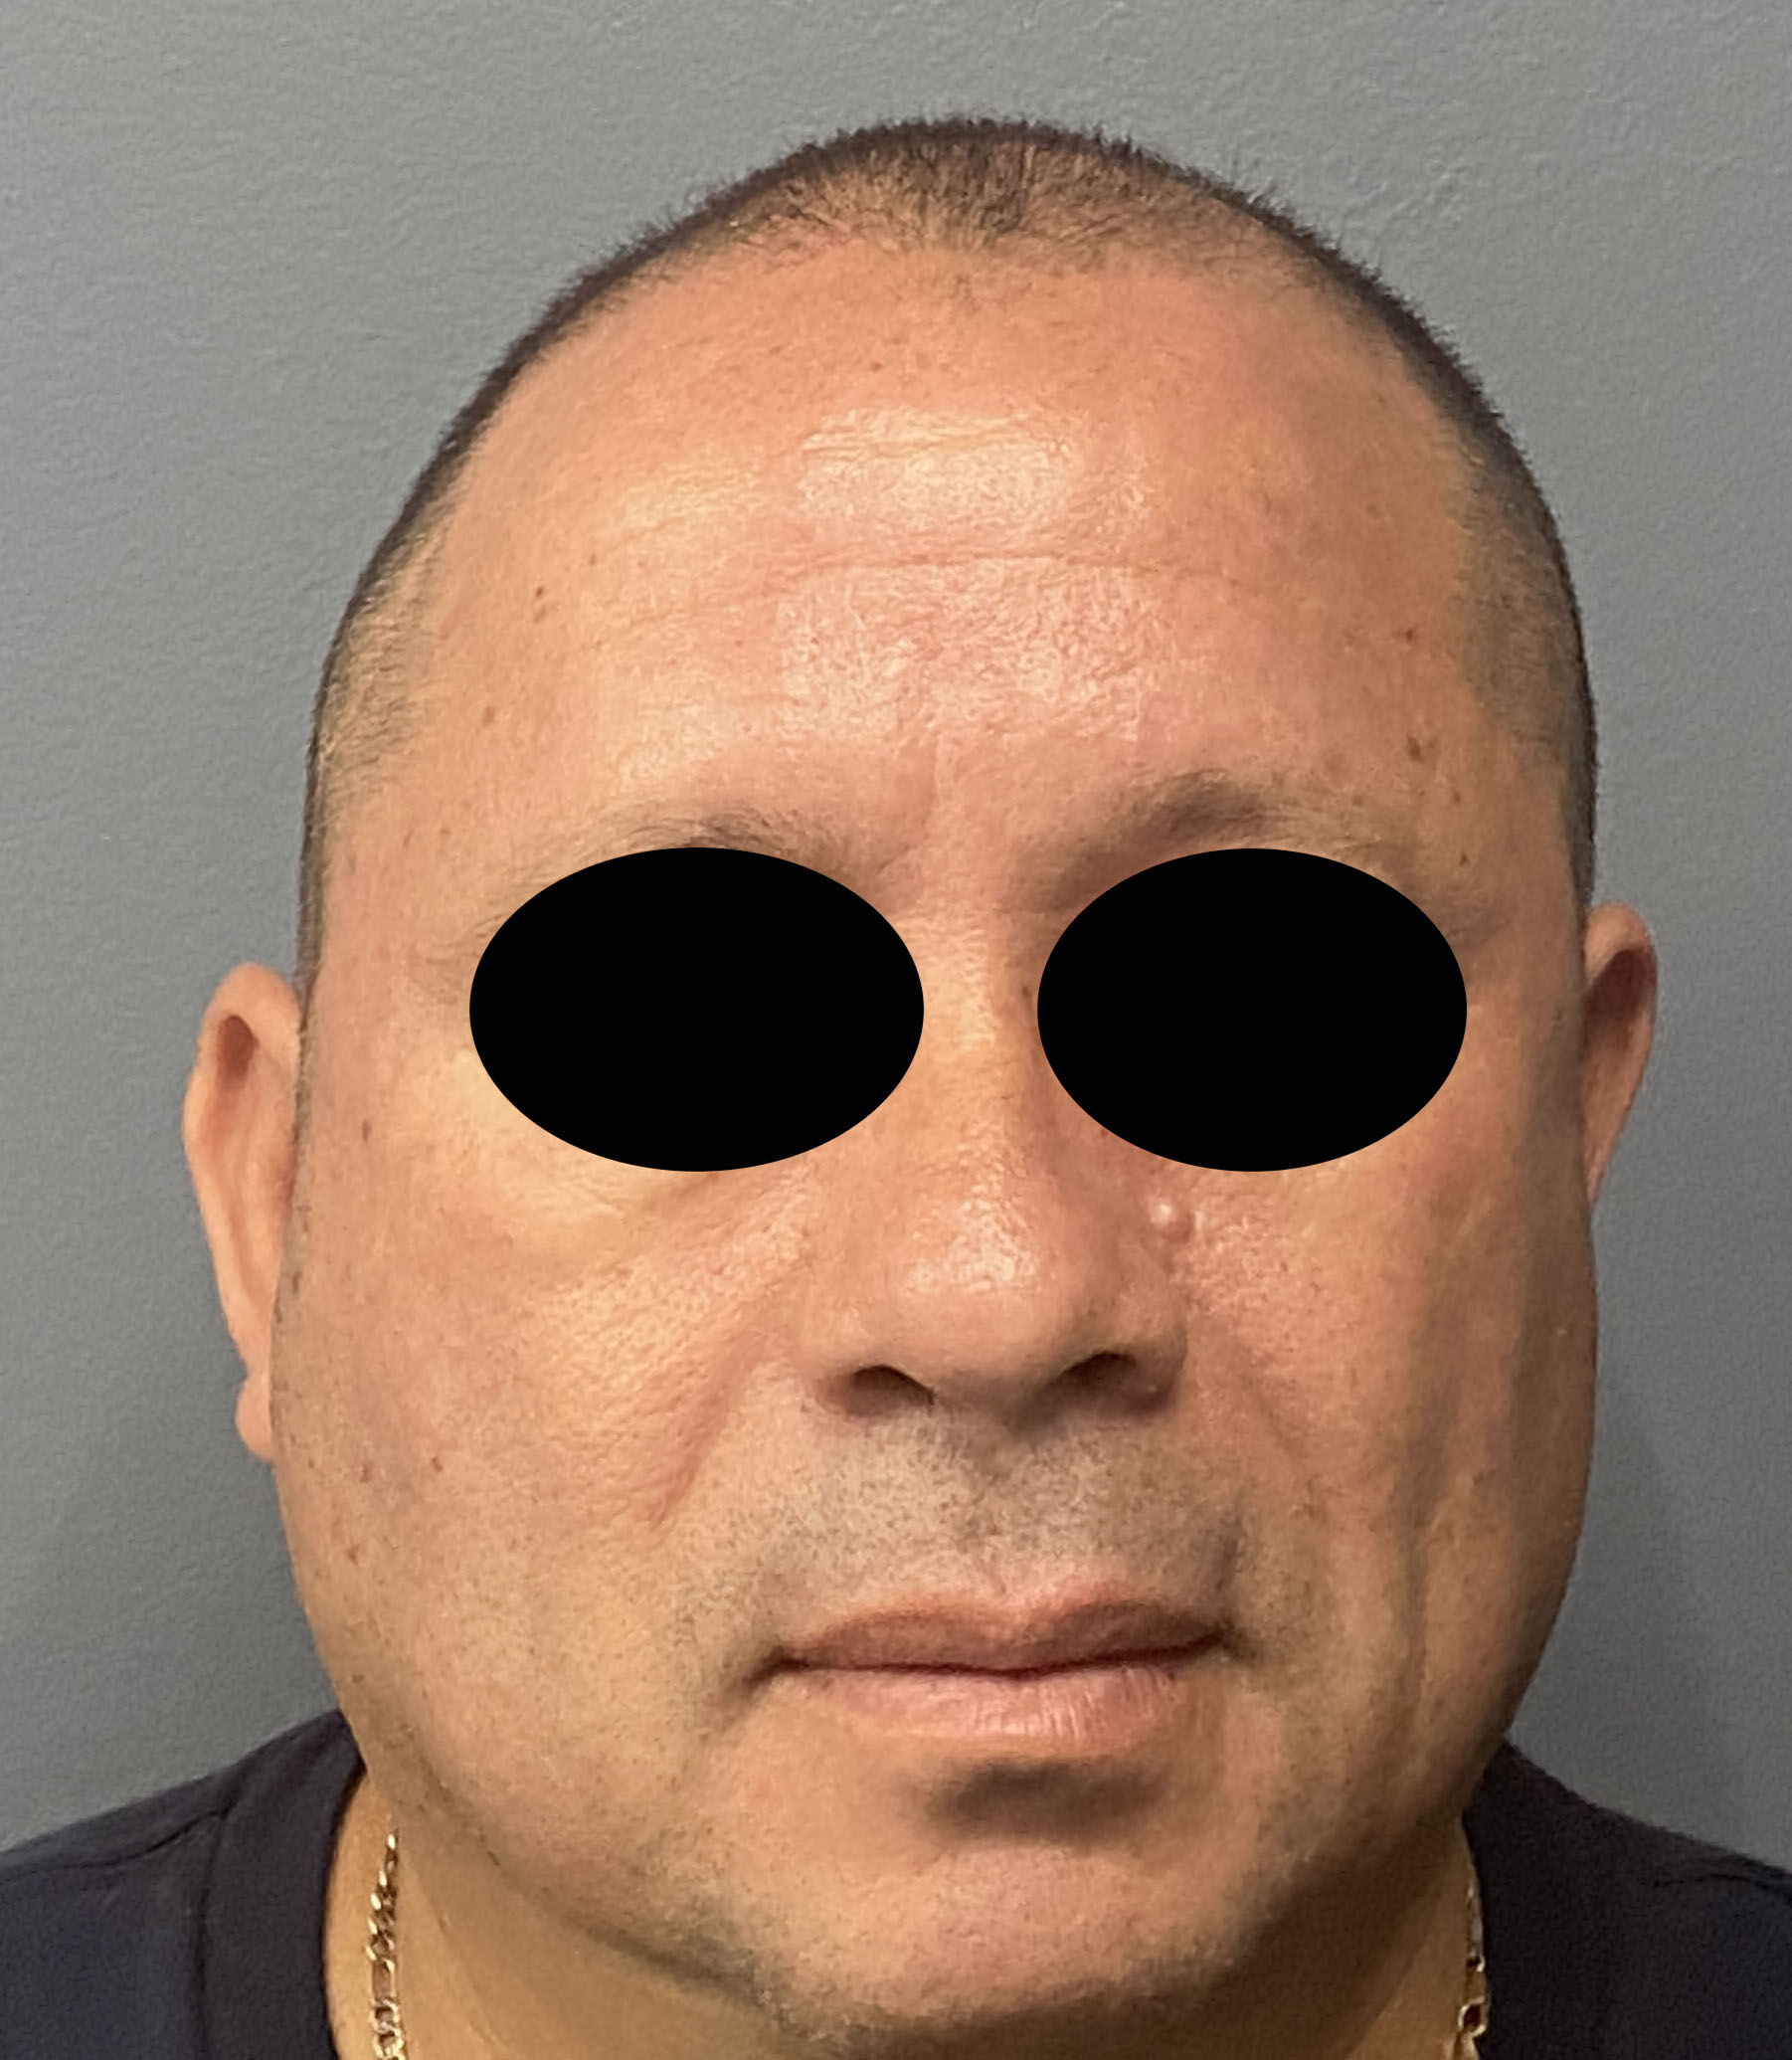

Patient 100

Desire for reshaping of an asymmetric flat back of the head in a shaved head male.

A combined back of the head reshaping procedure was done with a custom skull implant, sagittal ridge reduction and a right temporal muscle reduction.

Desire for reshaping of an asymmetric flat back of the head in a shaved head male.

A combined back of the head reshaping procedure was done with a custom skull implant, sagittal ridge reduction and a right temporal muscle reduction.